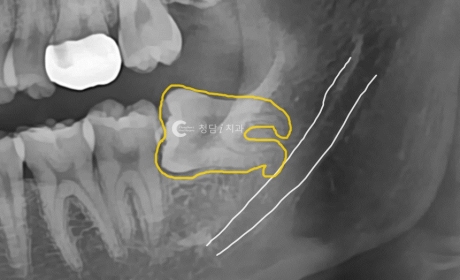

이것은 사랑니와 작은어금니만을 엑스레이로 촬영한 것입니다. 염증이 진행된 지 어느 정도 시간이 지난 것으로 보이며, 염증 초기에는 환자가 별다른 불편함을 느끼지 않는 것 같았으나, 염증이 진행됨에 따라 점차 잇몸뼈가 녹아내리면서 치아가 조금씩 진동하게 되었습니다.

주황색 선이 보이면 잇몸선을 확인한 것입니다. 사랑니만 뽑았으면 이 치아를 유지해도 괜찮았을 텐데 이미 염증이 너무 커서 치아 뿌리가 녹아 없어졌습니다.